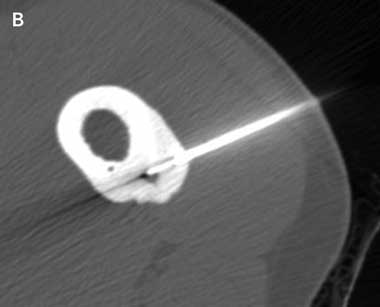

An insulated SMK C-15 electrode (Radionics, Burlington, Mass, USA) was inserted through the Bonopty cannula into the lesion and its position confirmed by CT imaging. Thermal coagulation to 90°C for 6 minutes was achieved using a radiofrequency generator (Radionics RFG-3B, Burlington, Mass, USA) as described by Rosenthal et al4 (Box 1A and Box 1B). If the nidus was larger than 10 mm in maximum diameter, the electrode was repositioned within the nidus and further burns were performed to cover the entire nidus. As the needle entered the nidus and ablation was commenced, elevation of the patients’ resting pulse rate by 10–20 beats/minute was commonly observed. At completion of the procedure an adhesive dressing was applied.